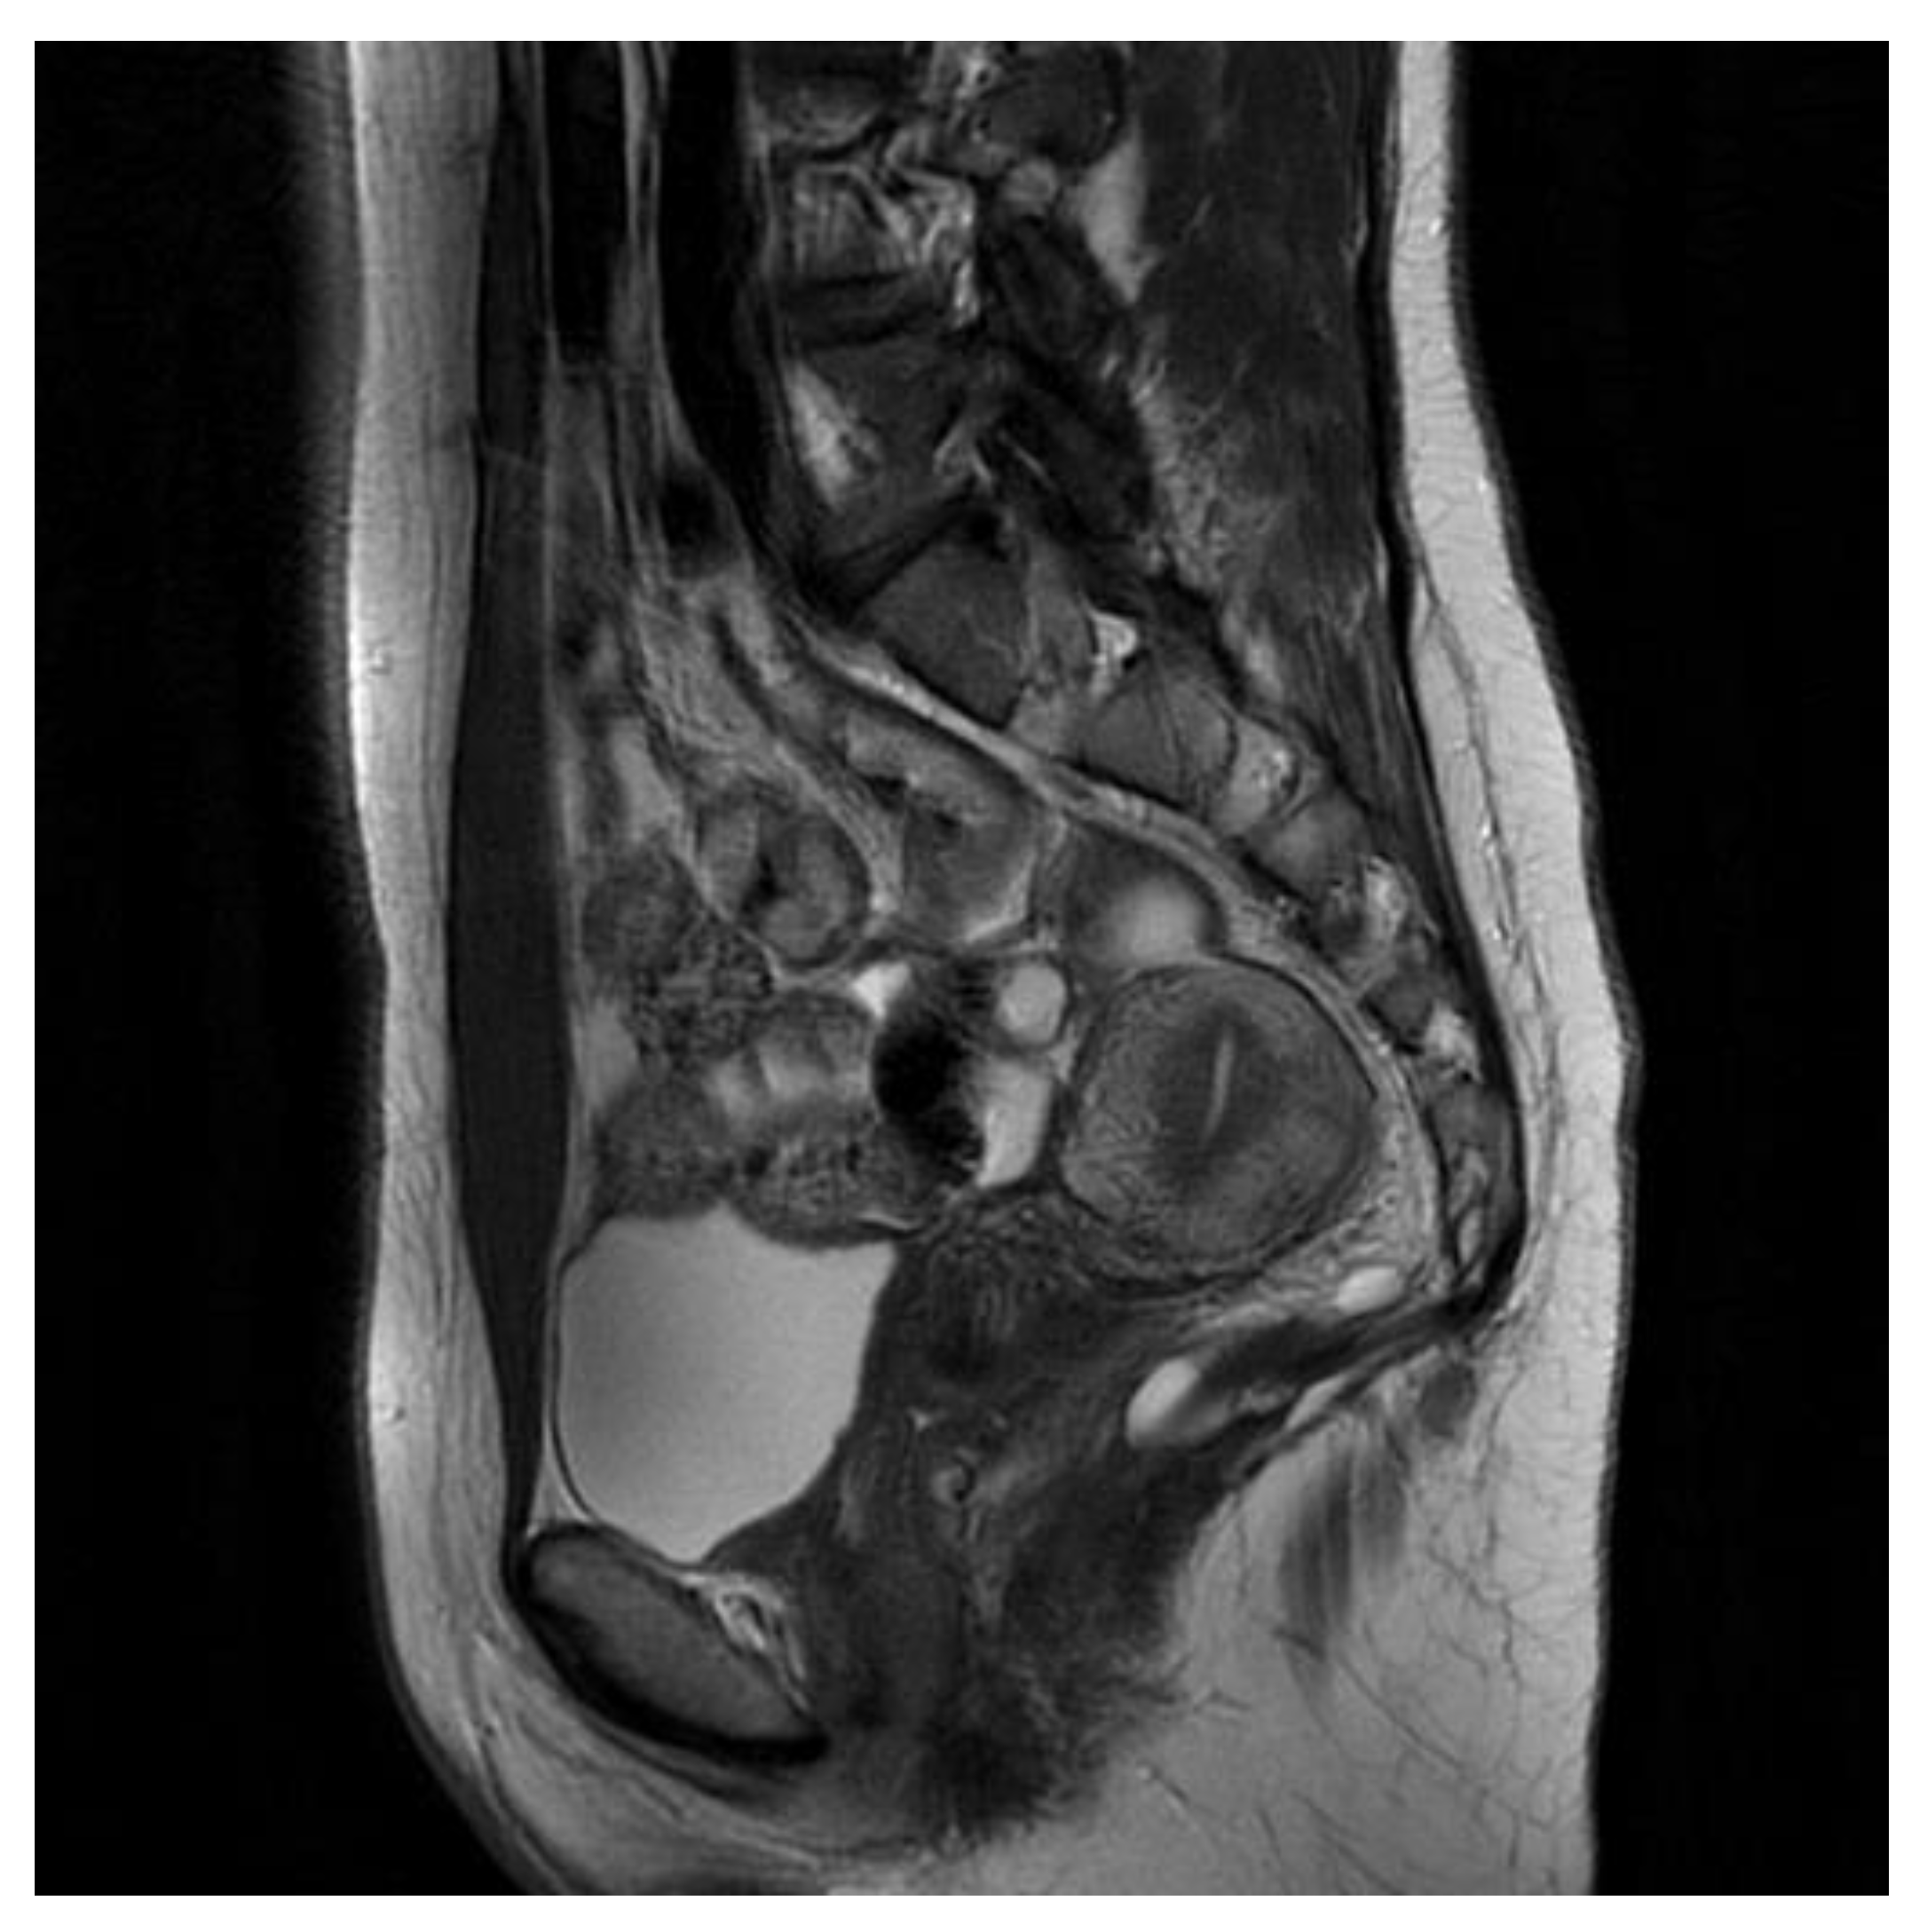

The first patient is a 40-year-old woman with large intestinal hyperplastic polyps and hemorrhoids. The pelvis minor tumor was diagnosed in 2016 during a routine ultrasound, and the patient underwent an unsuccessful surgery the same year. The tumor was asymptomatic, but in 2021, the patient started to experience morning tenesmus, urinary outflow disorders and painful ovulation. The physical examination showed left-sided thickness in a per vaginam examination. An MRI scan the with contrast of the lesser pelvis revealed a cystic, multilocular mass measuring 8.9 cm × 8.1 cm× 6.3 cm. This lesion shifted the rectum forward and to the left. It pressured the reproductive organ. The MRI scan aroused suspicion of a tailgut cyst [Figure 1].

Figure 1. First patient MRI scan of the lesser pelvis. Green arrow shows the lesion.